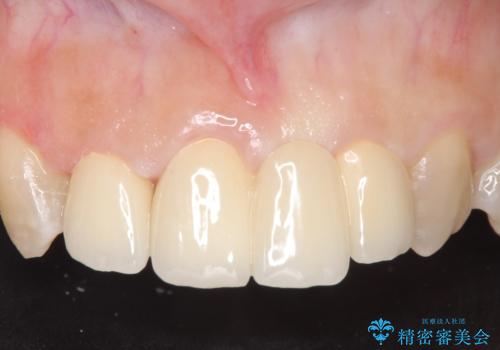

- 前歯の歯並びや色が気になるといらっしゃった方の症例です。

前歯4本をオールセラミッククラウンで補綴することで、歯の並びや色の改善を行いました。

今回用いたオールセラミッククラウンはジルコニアフレームという白い素材の上にセラミックを盛っているため、審美性が非常に高いのが特徴です。

また、ジルコニアは人工ダイヤモンドの材料にも使われているほど高い強度を持っており、そのためオールセラミッククラウンは審美性だけでなく、奥歯やブリッジの補綴も可能とするクラウンです。